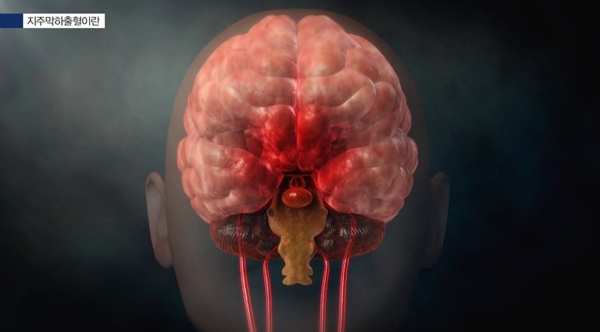

오늘은 생명과도 연결되는 뇌졸중 전조증상에 대해 알려드리겠습니다. 뇌 손상을 유발하는 대표적인 질환이 뇌졸중입니다. 뇌졸중은 뇌혈관이 막히거나 터져서 나타나는 문제입니다. 뇌혈관이 막히면 뇌경색, 뇌혈관이 터지면 뇌출혈이라고 불립니다. 산소 공급이 원활하지 않기 때문에 뇌세포가 손상될 가능성이 매우 높습니다. 뇌세포 손상 정도에 따라 다양한 합병증이 나타납니다.

뇌졸중은 뇌에 피가 통하지 않거나 뇌에 연결된 혈관이 파열되어 발생하는 증상을 말하는데, 이로 인해 뇌의 기능에 장애가 생기고 몸에 장애가 생기거나 심하면 사망에 이르는 질환입니다. 뇌졸중이 발생하면 뇌신경에 이상이 생기기 때문에 손상된 뇌 부위에 연결된 신체 부위도 움직이기 어려워집니다.